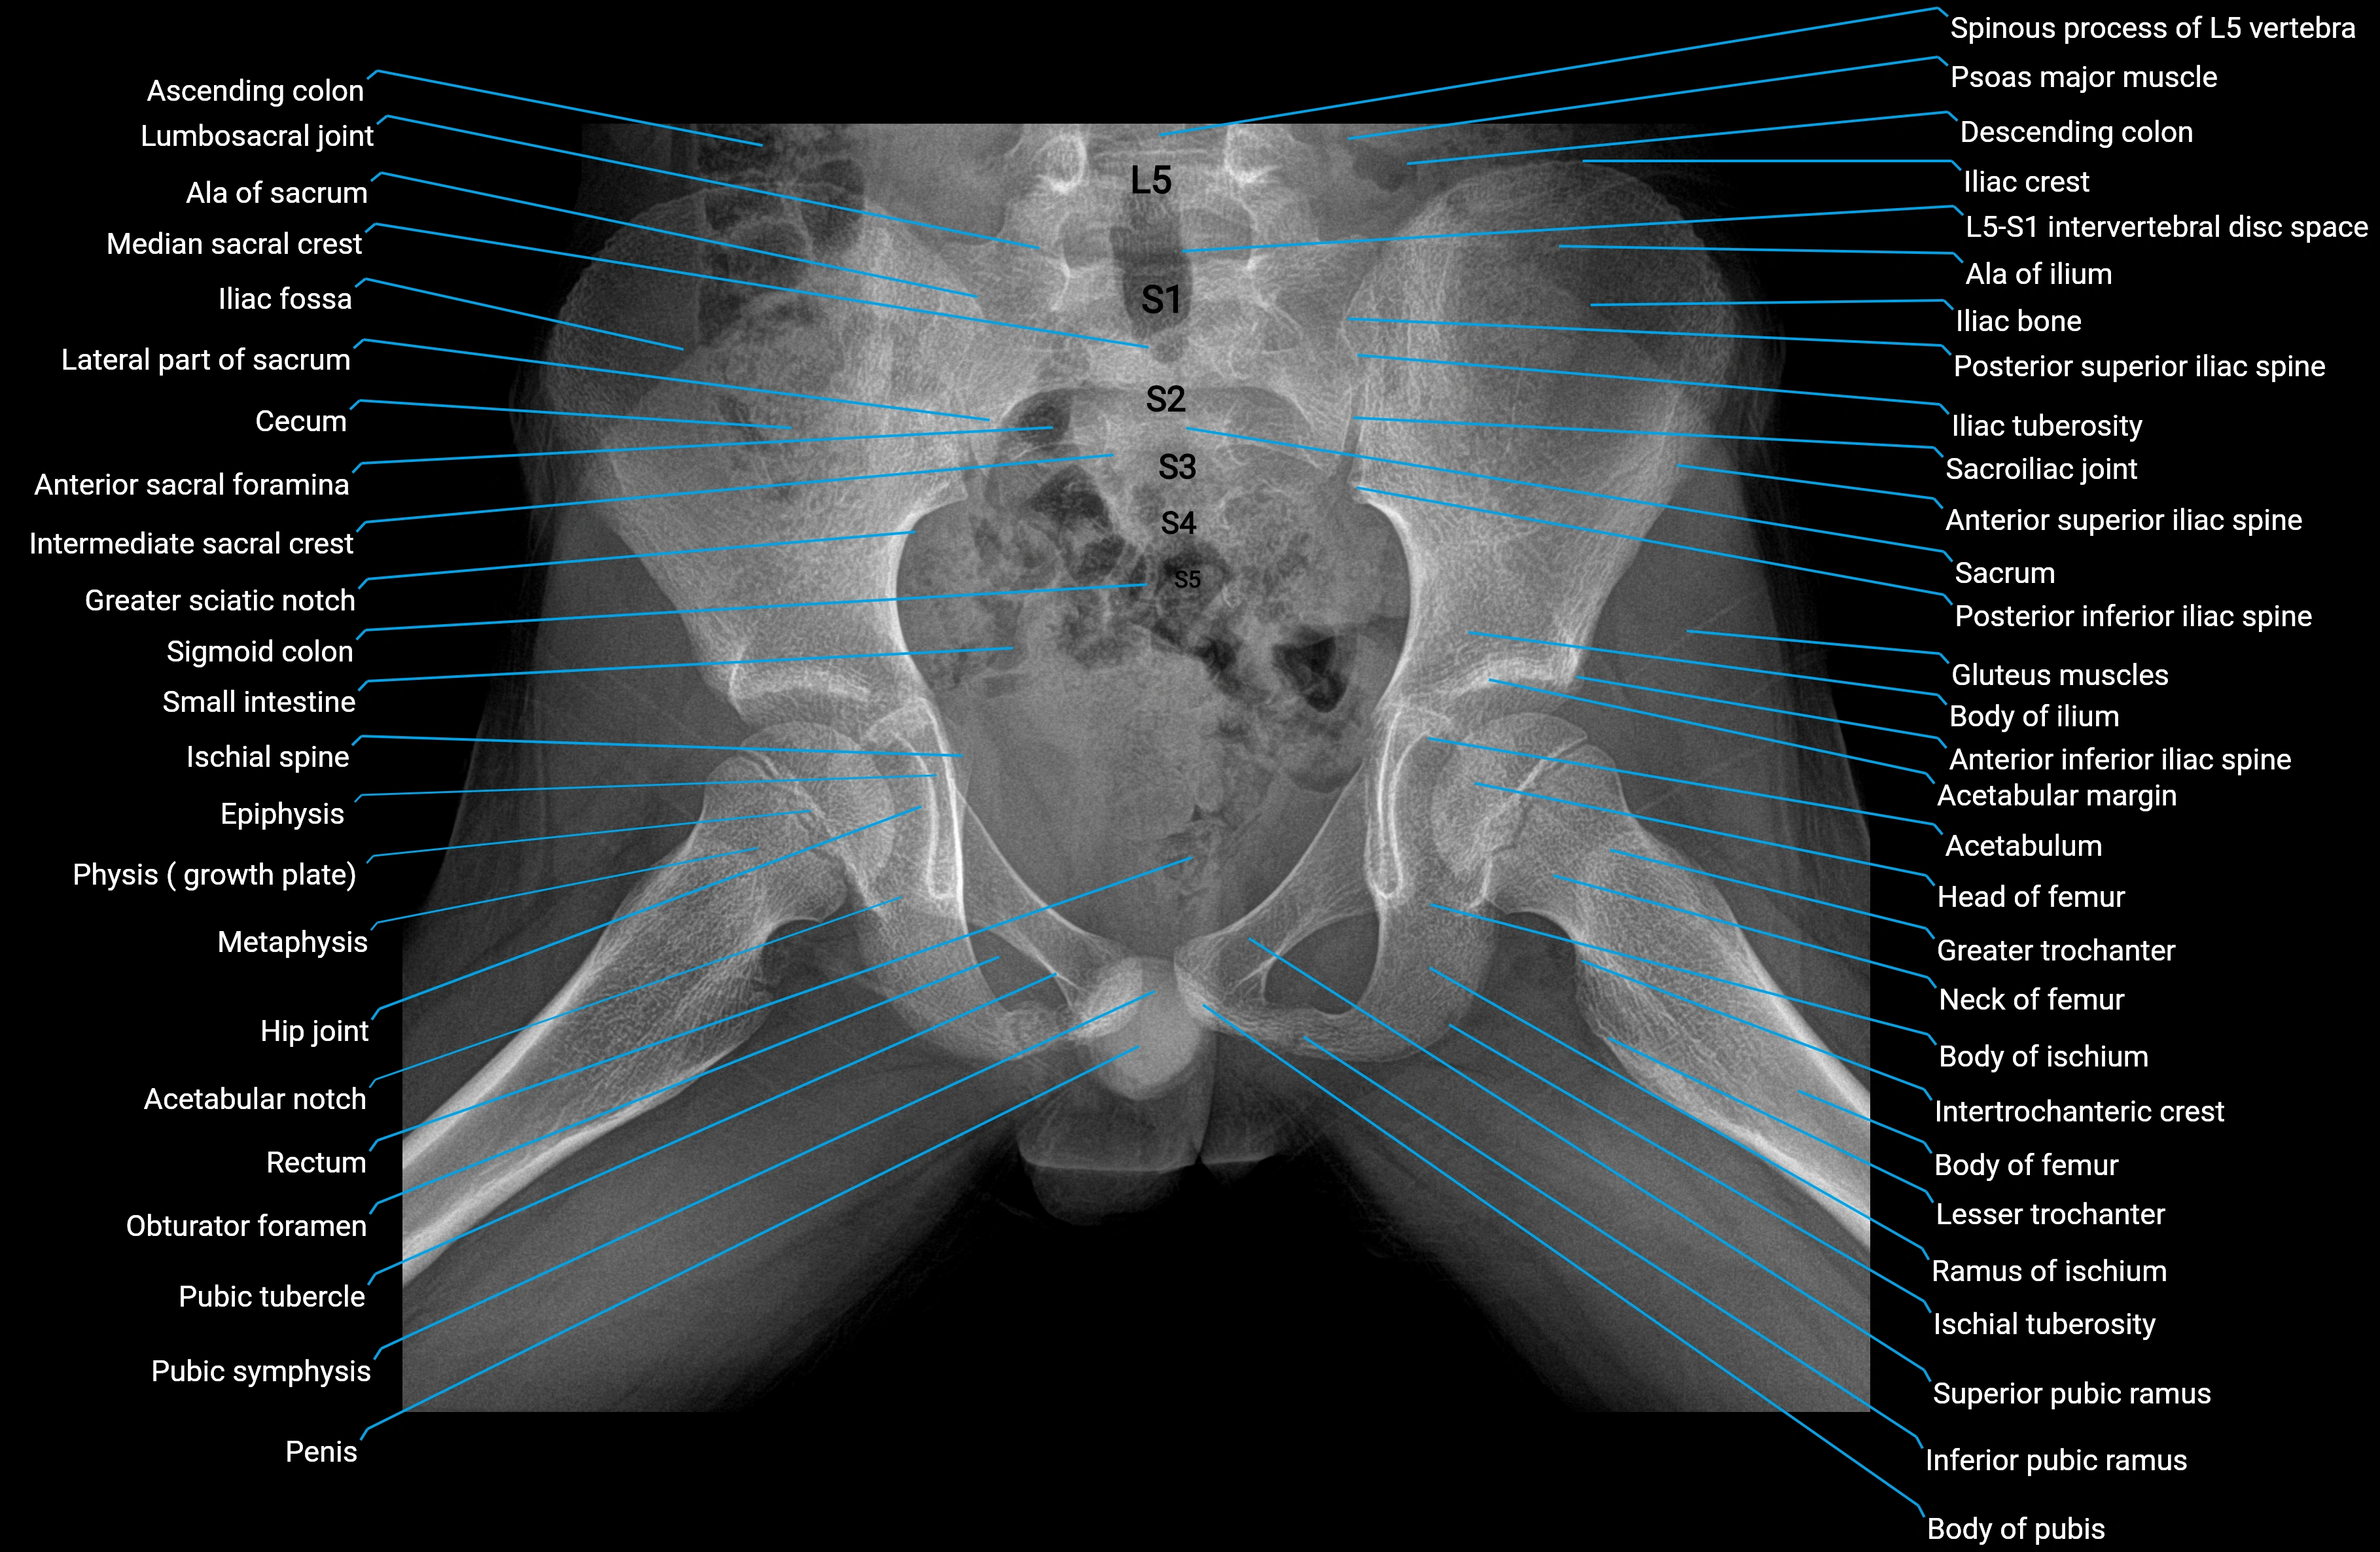

- Acetabular margin (Acetabular rim)

- Acetabulum

- Ala of ilium (wing of ilium)

- Ala of sacrum

- Anterior inferior iliac spine

- Anterior sacral foramina

- Anterior superior iliac spine

- Ascending colon

- Body of femur

- Body of ilium

- Body of ischium

- Body of pubis

- Cecum

- Descending colon

- Fovea for ligament of head of femur

- Gluteus medius muscle

- Gluteus minimus muscle

- Gracilis muscle

- Greater sciatic notch

- Greater trochanter

- Head of femur

- Hip joint

- Iliac bone

- Iliac crest

- Iliac fossa

- Iliac tuberosity

- Iliopsoas muscle

- Inferior articular process of vertebra

- Inferior pubic ramus

- Intermediate sacral crest

- Intertrochanteric crest

- Ischial spine

- Ischial tuberosity

- L (Lumbar spine)

- Lateral part of sacrum

- Lateral sacral crest

- Lesser trochanter

- Lumbosacral joint

- Median sacral crest

- Neck of femur

- Neck of urinary bladder

- Obturator foramen

- Obturator internus muscle

- Penis

- Posterior inferior iliac spine

- Posterior superior iliac spine

- Psoas major muscle

- Pubic symphysis

- Pubic tubercle

- Ramus of ischium

- Rectum

- S (Sacral spine)

- Sacrococcygeal joint

- Sacroiliac joint

- Sacrum

- Shenton’s line

- Sigmoid colon

- Small intestine

- Spinous process of vertebra

- Superior pubic ramus